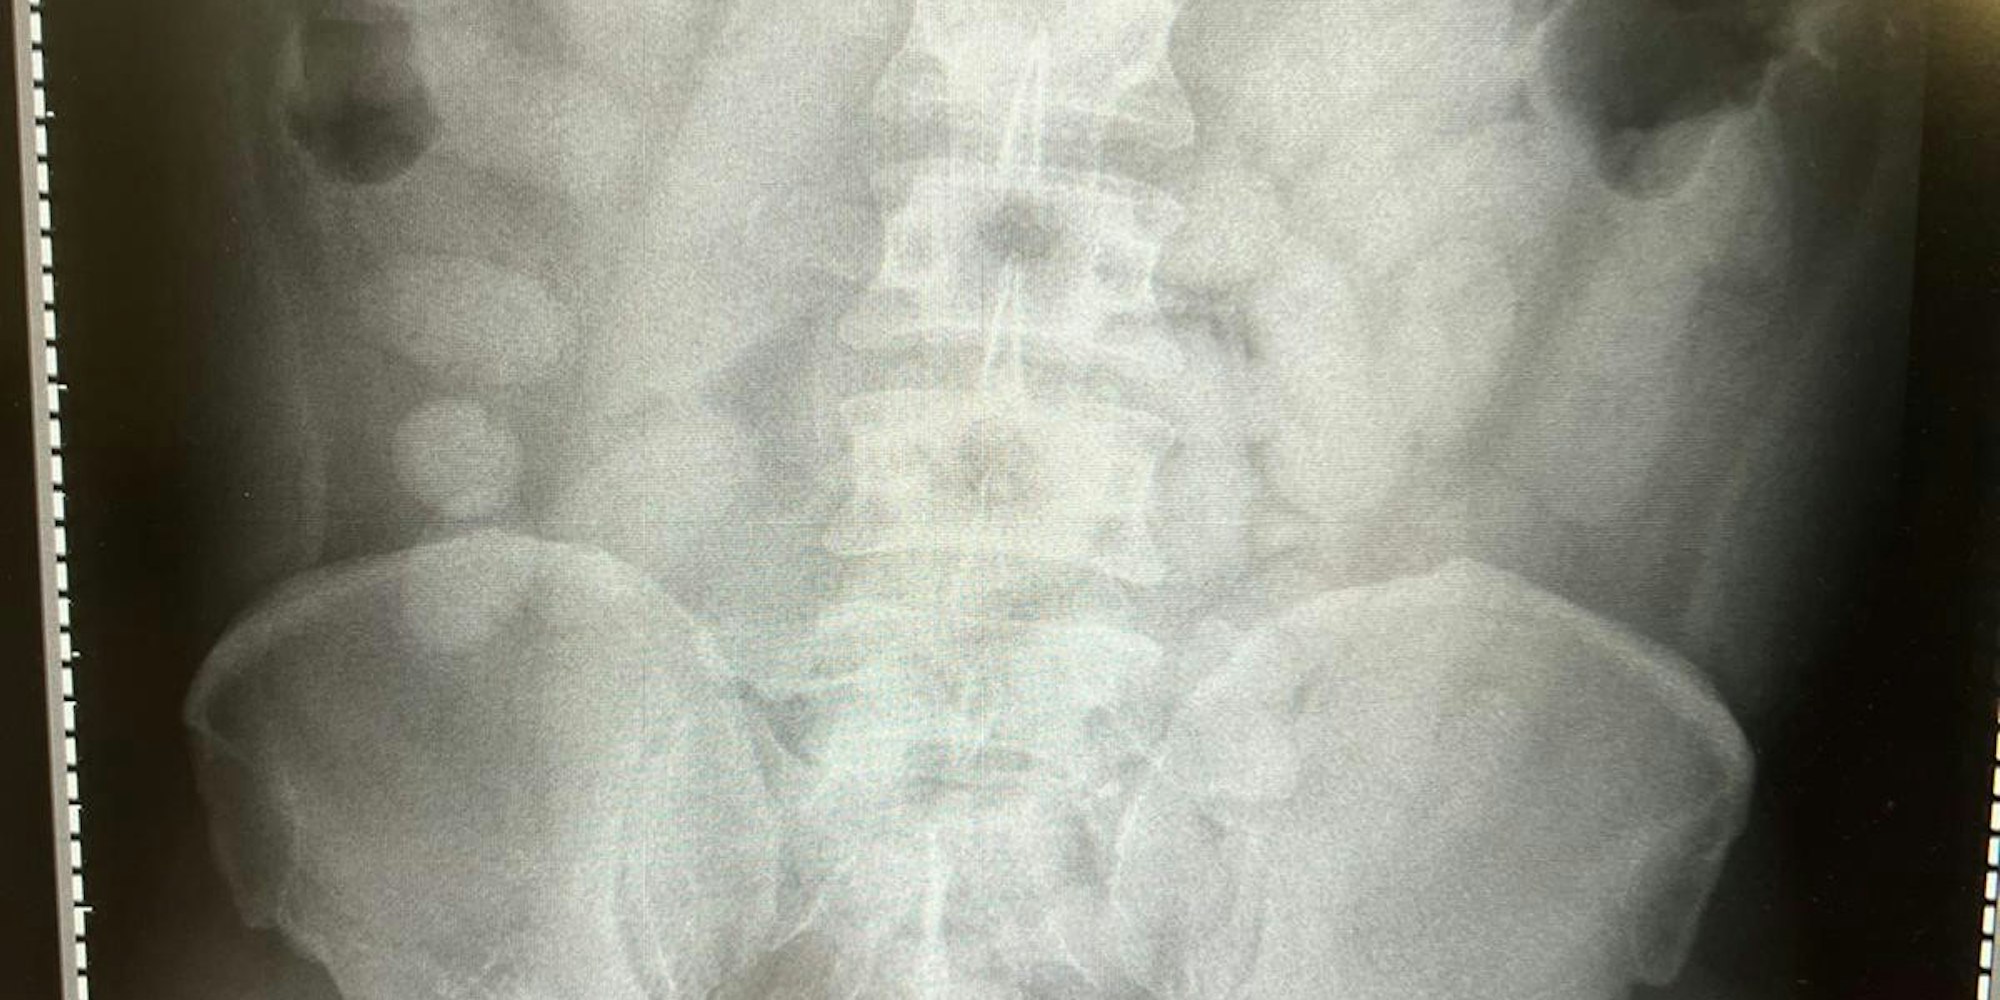

Diesen Röntgenbild des Körperschmugglers veröffentlichte das Hauptzollamt.

„Die Röntgenaufnahme in einem nahe gelegenen Krankenhaus bestätigte letztendlich den Verdacht“, so Jens Ahland, Sprecher des Hauptzollamtes. „Der komplette Magen-Darm-Trakt des Mannes war voll mit Drogenpäckchen, sogenannten Bodypacks.“ Insgesamt seien es 72 Stück mit jeweils knapp 14 Gramm Kokain gewesen. Wäre nur eines aufgegangen, wäre das Leben des Mannes nicht mehr zu retten gewesen, betonte Ahland. Die Ermittlungen dauern an (csc)